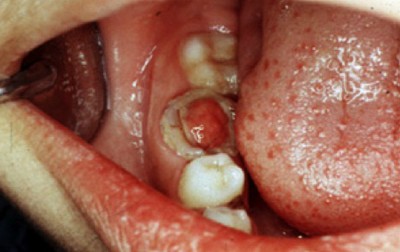

Пульпарный абсцесс

Скопление гноя в камере пульпы. После повышения в пульпе уровня серозного вещества происходит кислородная недостаточность.

Фото 1. Так выглядит осложнение пульпита, пульпарный абсцесс: на десне верхней челюсти заметно скопление гноя.

Нарушенный кислотно-щелочной баланс увеличивает количество молочной кислоты, что угнетает защитную клеточную функцию. Начинается распад тканей, и появляются симптомы абсцесса.